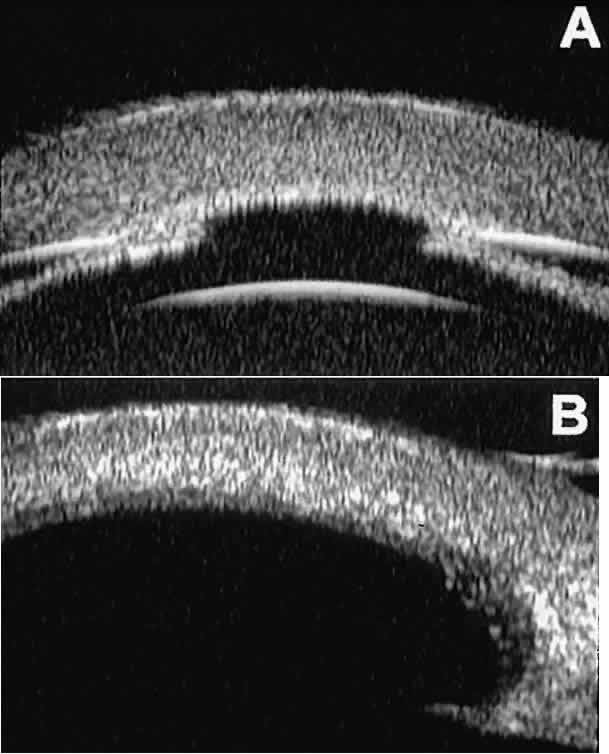

After any type of glaucoma filtering surgery,10 UBM can be used to detect and evaluate the extent of postoperative complications such as ciliochoroidal effusion and cyclodialysis.3,4 In ciliochoroidal effusion (Fig. 13A), UBM shows the ciliary body to be edematous and separated from the sclera by a sonolucent collection of supraciliary fluid. Many ciliochoroidal effusions that are too limited in extent to be detectable by indirect ophthalmoscopy and slit lamp biomicroscopy can be imaged by UBM. In cyclodialysis (see Fig. 13B), UBM shows a well-defined separation between the uveal tissue and the sclera in the region of the scleral spur. The width of the cleft is usually assessed best by means of limbus-concentric images through the region of interest.

Fig. 13. Complications of intraocular surgery. A. Postoperative ciliochoroidal effusion appears as slitlike spaces filled with serous fluid posterior to scleral spur. B. Postoperative cyclodialysis appears as complete separation of iris and ciliary body from sclera in region of scleral spur.